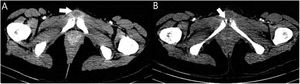

A 19-year-old woman who, after treatment for acute tonsillitis, went to A&E with continuous pain in the pubic area. A chest X-ray was performed that revealed pseudonodular condensations (Fig. 1A), complementing the study with computed tomography (CT), which confirmed the presence of septic emboli (Fig. 1B and C), for which the patient was admitted. An ultrasound of the neck ruled out thrombophlebitis of the jugular vein. A blood culture was obtained and intravenous broad-spectrum antibiotic therapy with meropenem and linezolid (1 g/8 h and 600 mg/12 h, respectively) was prescribed. A pelvic CT confirmed the presence of pubic symphysitis (osteitis pubis) with abscessification (Fig. 2). Surgical cleaning with debridement was performed, and two samples were sent for culture.